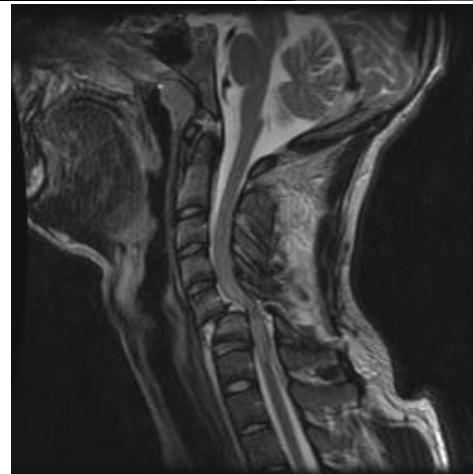

- MRI: Rarely indicated as these fractures are usually not associated with neurologic symptoms

- MRI: Should be performed before surgery to identify associated disk herniation